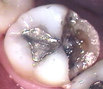

Large old fillings. When large old fillings break down, or get decay around them, they usually need to be crowned. It is important to crown a tooth that has been structurally weakened to prevent a cracked or broken tooth. Once a tooth breaks, it may not be possible to save it.

old filling